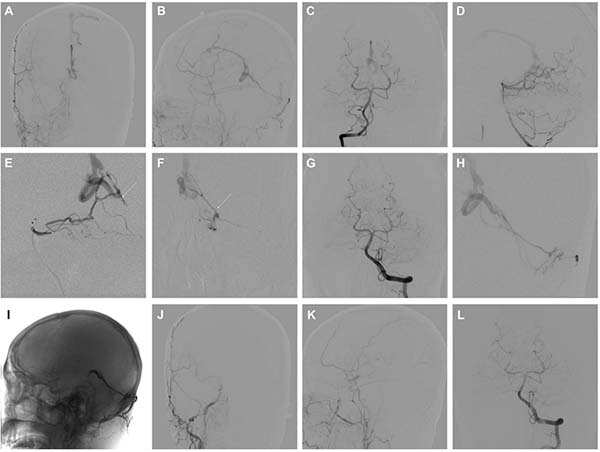

图3. A-D:正位和侧位的颈外动脉及椎动脉造影显示,位于Galen区的Borden III型DAVF,同时可见直窦不显影。E和F:左侧大脑后动脉的超选造影显示一条线状扩张的供血动脉,考虑为起源于PAS的硬膜分支(白箭头所示)。G:在将微导管尽可能靠近至瘘口附近后,注入Glubran进行栓塞,成功实现对大脑后动脉供血动脉的完全闭塞。H:枕动脉的超选造影。I:通过枕动脉使用Onyx对DAVF进行完全闭塞后形成的栓塞剂铸型影像。J-L:术后即刻造影显示DAVF已完全闭塞,患者术后无明显不适。

图4. A-F:颈外动脉、颈内动脉及椎动脉的正位和侧位造影显示一例高级别的中线天幕区DAVF,引流入异常扩张的、静脉瘤样结构,提示为高风险病灶。G:右侧大脑后动脉的超选造影显示一条曲折分支的供血动脉,提示为“纯”软膜供血(白箭头所示)。H:为降低脑梗死相关并发症的风险,将微导管尖端尽量靠近至瘘口附近后注入Glubran进行栓塞,成功实现对大脑后动脉起源的“纯”软膜供血的完全闭塞。I和J:随后通过枕动脉注入Onyx进行栓塞,成功闭塞了瘘口及引流静脉的近端部分。K和L:术后即刻造影显示DAVF完全闭塞,未见脑缺血或出血相关并发症。